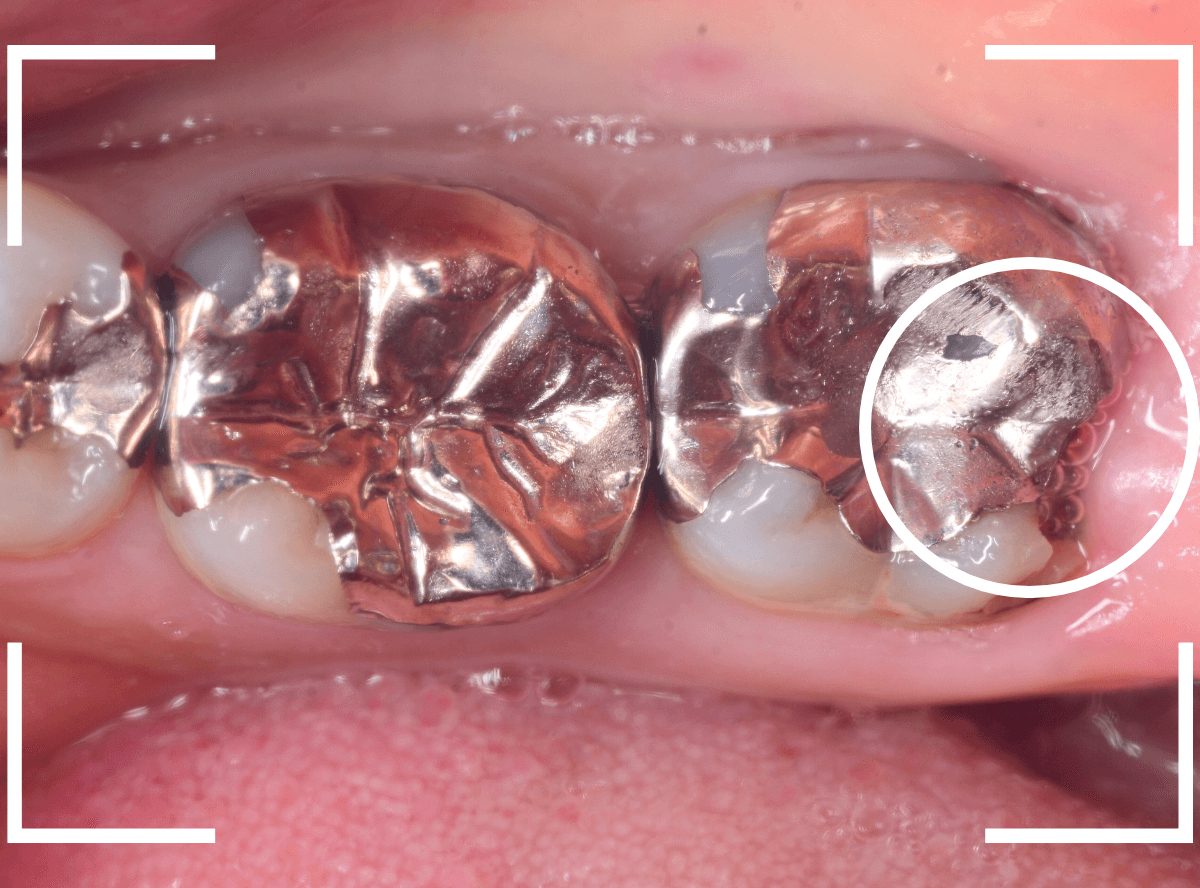

Case.14 インレーの下の歯肉まで広がった虫歯

「下の奥歯が噛むと痛む」という症状で来院された患者さんのケースです。

お口の中の状態を確認すると、奥歯の端に穴が開いているのが見えます。

ここかな?

レントゲン写真で確認します。

やはり、奥歯の端が大きな虫歯になっています。

青いラインが歯の神経、赤いラインが虫歯です。

レントゲン写真上では虫歯が神経まで達しているように見えます。

これは、神経を取らないとダメかもしれません。